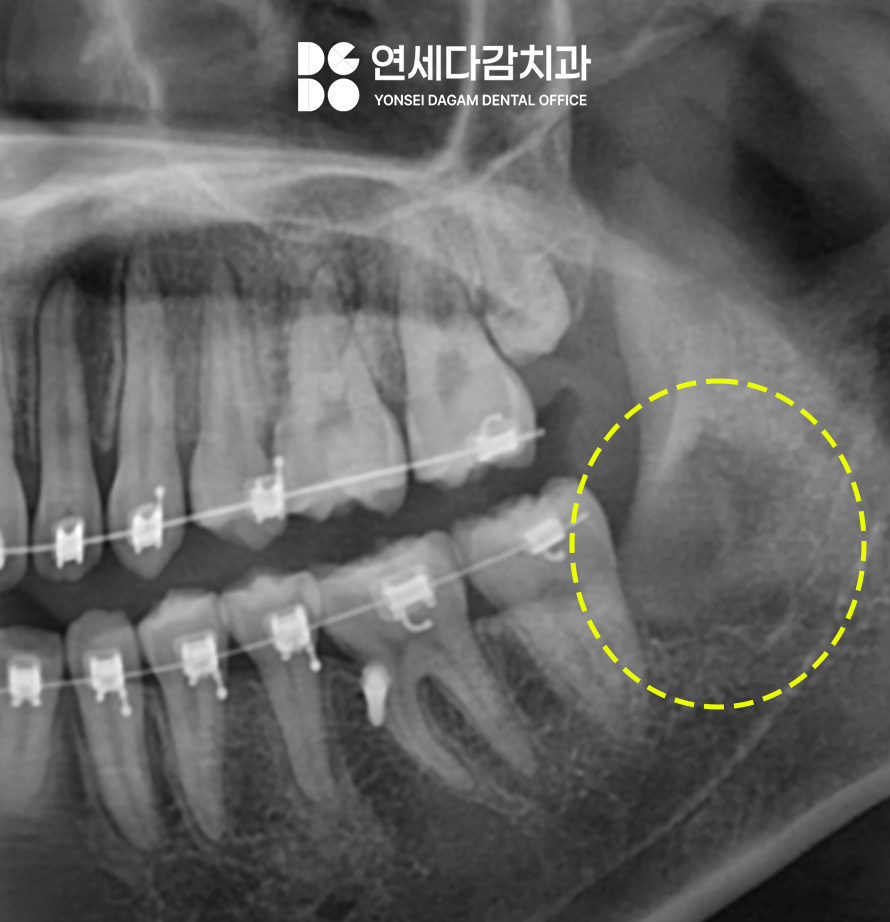

오금동 치과 에서 촬영한

파노라마 사진을 보면,

사랑니 4개가 모두

존재하고 있습니다.

CT를 살펴보면 교합면(치아의 윗면)이

설측으로 수평 매복된 형태였습니다.

현재 위턱에 표시된 부위가

정상적으로 맹출 되고 있지 않은 상태로,

현재는 정출 유도 장치를 이용하여

경과를 관찰 중입니다.

정출시키는 과정에서 옆에 있는

사랑니가 물리적으로

방해된다고 판단되면,

필요시 추가 조치를 시행할

예정입니다.